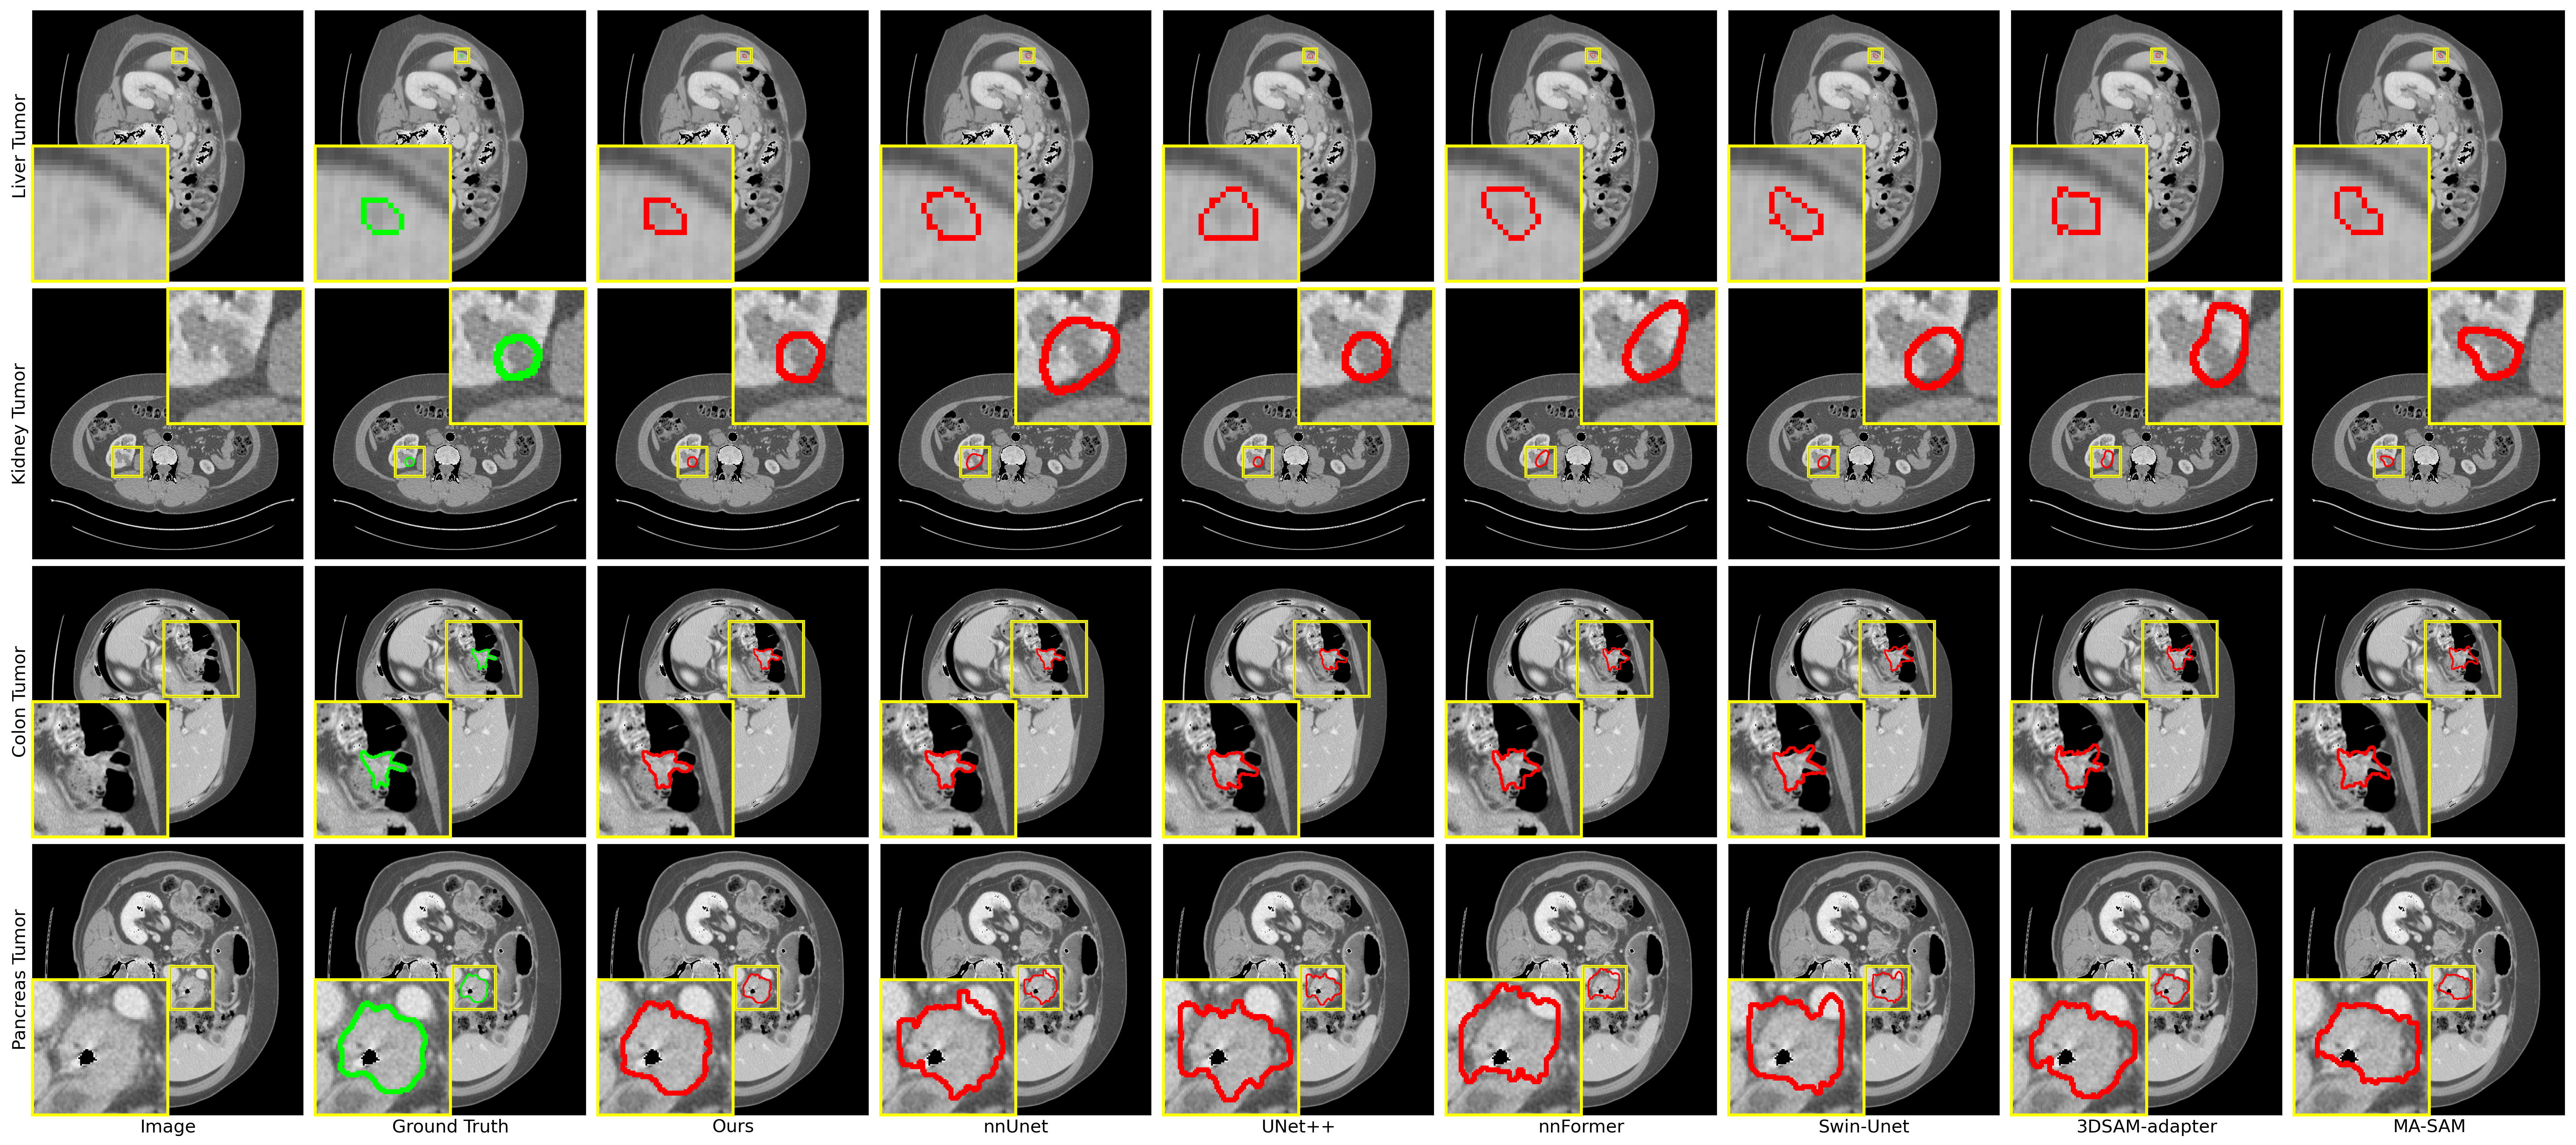

Refer to caption

Figure 3: Qualitative visualizations of the proposed method and baseline approaches on liver tumor, kidney tumor, pancreas tumor and colon cancer segmentation tasks.

The results presented in Table I demonstrate that our proposed Ref-SAM3D method consistently outperforms other approaches across a wide range of tasks, achieving the highest scores in nearly all scenarios, particularly excelling in challenging tumor types. In the task of kidney tumor segmentation, despite challenges such as low contrast with surrounding tissues, blurred boundaries, and high morphological heterogeneity, Ref-SAM3D achieved a DICE score of 95.53% and an NSD of 99.45%, surpassing other methods. For pancreatic tumors, which constitute less than 0.5% of CT images and exhibit diverse shapes, Ref-SAM3D achieved a DICE score of 82.42%, representing a 2.12% improvement over existing SOTA techniques. In liver tumor segmentation, Ref-SAM3D attained a DICE score of 80.10%, effectively handling variations in grayscale and irregular shapes. Despite the extensive distribution and complex anatomical structure of colorectal cancer lesions, Ref-SAM3D achieved a DICE score of 70.14%, marking a 10.11% increase over current technologies. It is noteworthy that traditional methods like nnU-Net perform well on certain tasks, yet overall, they fall short compared to newer methods such as Ref-SAM3D. Particularly when dealing with tumors that have blurred boundaries and diverse morphologies, Ref-SAM3D demonstrates significant advantages. These findings underscore the exceptional performance of Ref-SAM3D in addressing a variety of complex medical image segmentation challenge. Figure 3 shows qualitative visualizations of theses tasks.